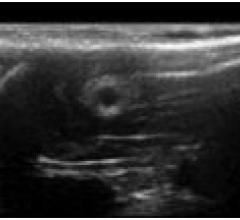

August 25, 2014 — New simple and effective methods are needed to better evaluate the outcomes of repair using nerve ...